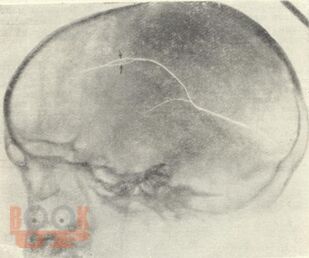

В методических рекомендациях в виде краткого реферата представлены введение, общее понятие о черепно-мозговой травме, частоте таких повреждений и их последствиях. Подробно описана классификация травматических повреждений черепа и головного мозга: 1) закрытая травма без повреждений и с повреждением костей черепа, 2) открытая травма черепа и головного мозга – непроникающая и проникающая. Выделены сотрясение, ушиб и сдавление головного мозга. Основное внимание в методических рекомендациях уделено методике рентгенологического исследования, разновидностям переломов черепа, их дифференциальной диагностике и последствиям черепно-мозговой травме. Приведен краткий литературный список. Методические рекомендации предназначены для интернов, ординаторов, рентгенологов.